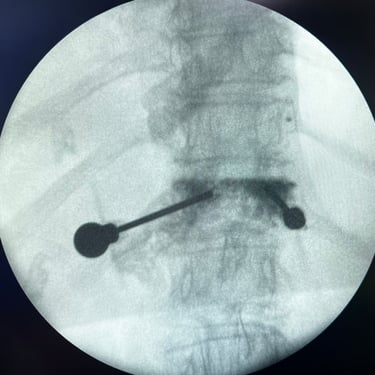

🧠 Artrodesis Lumbar Percutánea | Fijación mínimamente invasiva.

La artrodesis lumbar percutánea estabiliza la columna mediante tornillos y barras colocados por pequeñas incisiones, con mínima agresión muscular. Indicada en inestabilidad, fracturas o listesis, ofrece menor dolor postoperatorio, menor sangrado y recuperación más rápida. Es una técnica eficaz y segura para mejorar la función y calidad de vida.